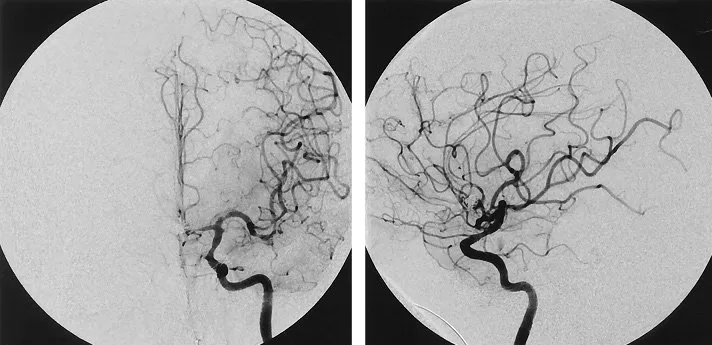

Tìm hiểu về kỹ thuật chụp mạch số hóa xóa nền (DSA) trong chẩn đoán và điều trị bệnh tim mạch. Bài viết trình bày định nghĩa, nguyên lý hoạt động, ưu điểm của DSA trong phát hiện sớm bệnh lý, hỗ trợ...